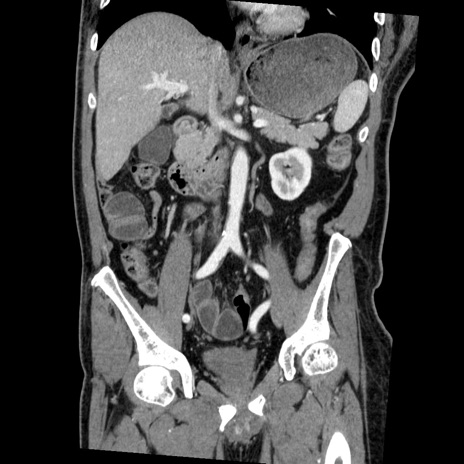

症例22(冠状断像)

【症例】50歳代男性

【主訴】腹痛

【現病歴】AVMからの被殻出血のため回復期リハ病棟入院中。 本日午後3時頃急に下腹部痛が出現した。

【既往歴】AVM、被殻出血、虫垂炎、高血圧

【身体所見】意識晴明、左半身不全麻痺、会話の理解は良好、36.5°C、腹部:膨隆、全体に板状硬、下腹部正中に圧痛点あり、反跳痛-、筋性防御不明、右下腹部にope scar

【データ】WBC 9400、CRP 0.06